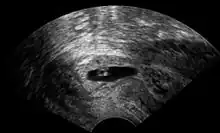

Vaginal ultrasonography of a cervical pregnancy at a gestational age of five weeks. See image below for details of the visible structures.[1]

The diagnosis is made in asymptomatic pregnant women either by inspection seeing a bluish discolored cervix or, more commonly, by obstetric ultrasonography. A typical non-specific symptom is vaginal bleeding during pregnancy. Ultrasound will show the location of the gestational sac in the cervix, while the uterine cavity is "empty". Cervical pregnancy can be confused with a miscarriage when pregnancy tissue is passing through the cervix.